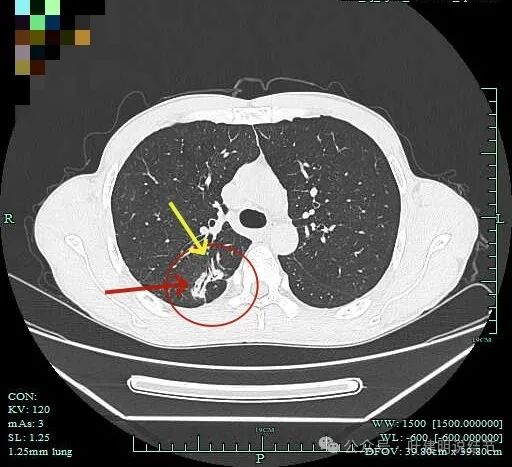

既往对比:

上图是2023年1月时的,虽也基本上实性,但明显病灶相对较小,而且膨胀感不太明显些。

到2023年9月病灶较前进展,或许测量大小变化不明显,但实性成分明显多起来,内部不太致密的部分明显显得较之前密了。

到了2024年5月,病灶整体给人感觉有收缩力了些,内部也更显致密了。

病灶1于2023年9月时都没有的,更说明是炎症性的。